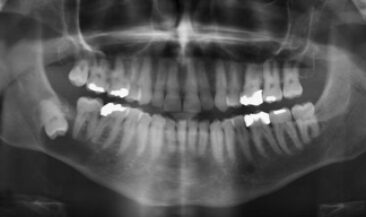

Wisdom tooth removal with enucleation of dentigerous cyst and bone graft